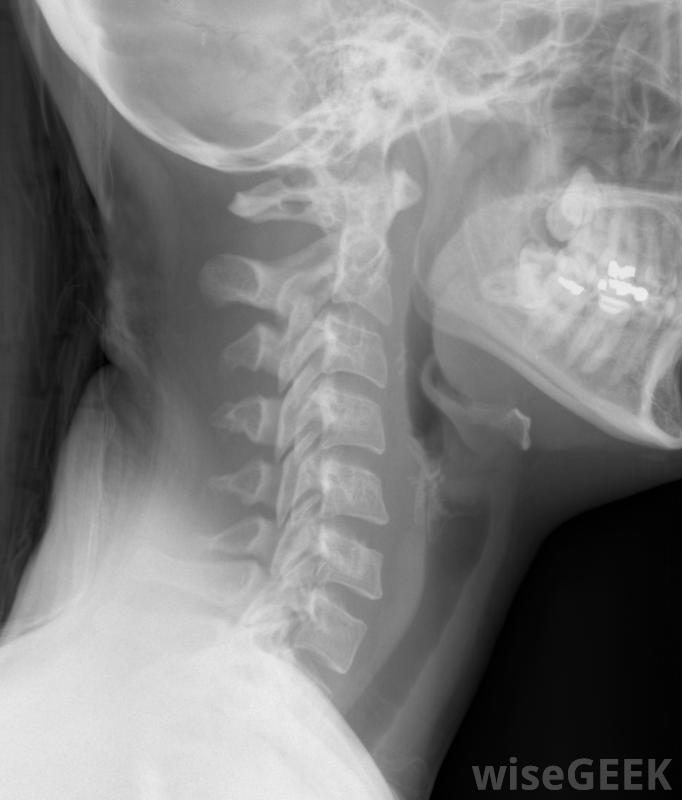

頸椎管狹窄癥是一種以頸椎椎管狹窄為特征的脊柱疾病。頸椎位于脊柱的頂部,背部和頸部的上部。椎管狹窄也可能發生在脊椎的其他部位,比如腰椎,頸椎管狹窄癥是一個非常嚴重的醫學問題,很多其他的脊椎疾病也是如此,有很多方法可以治療這種疾病,根據進展情況而定。頸部的X光片,包括頸椎頸椎管狹窄癥的常見原因僅僅是椎骨的磨損。隨著年齡的增長,椎骨間的填充物,即椎間盤,變得越來越不靈活,椎骨開始壓縮椎間盤。有些人的椎骨內側出現骨刺,這些骨刺伸入椎管,導致椎管狹窄,如果足夠狹窄,就會對脊髓造成損傷,脊髓損傷被稱為脊髓病,它會引起一些非常明顯的癥狀隨著年齡的增長,他們的脊椎會開始壓縮腰椎間盤。頸椎管狹窄癥患者會感到麻木、刺痛,偶爾也會有疼痛,因為神經在狹窄的椎管內受到擠壓和擠壓這就是所謂的頸神經根病。如果不解決這個問題,可能會造成嚴重的長期損害,患者的疼痛也會越來越嚴重。頸椎管狹窄通常是逐漸發生的,有時癥狀需要很長時間才能出現,因此當出現頸部疼痛、麻木和刺痛時,就醫非常重要,即使癥狀是間歇性的。頸椎管狹窄手術可能需要去除骨刺以幫助椎管變寬為了診斷頸椎管狹窄癥,醫生一般會詢問病人病史,并安排一系列的醫學影像學檢查。這些影像會顯示椎管狹窄。醫生也會進行一些神經檢查,以檢查神經損傷,以及為了確定狹窄的進展程度。宮頸狹窄有時會導致女性月經停止如果早期發現宮頸狹窄,有時可以通過藥物治療和有針對性的物理治療來治療。這些治療可以減緩或停止椎管狹窄,同時消除許多不舒服的狹窄癥狀。如果病情惡化或非手術治療無效,醫生會建議進行手術在手術中,通過切除部分骨刺使椎管變寬,可以減輕對脊髓的壓力。雖然很少見,但子宮頸狹窄的一個癥狀是痛經頸椎狹窄最常見的原因是椎骨的磨損上背部和頸部是頸部狹窄的常見癥狀。頸部狹窄患者可能會感到頸部刺痛和刺痛。